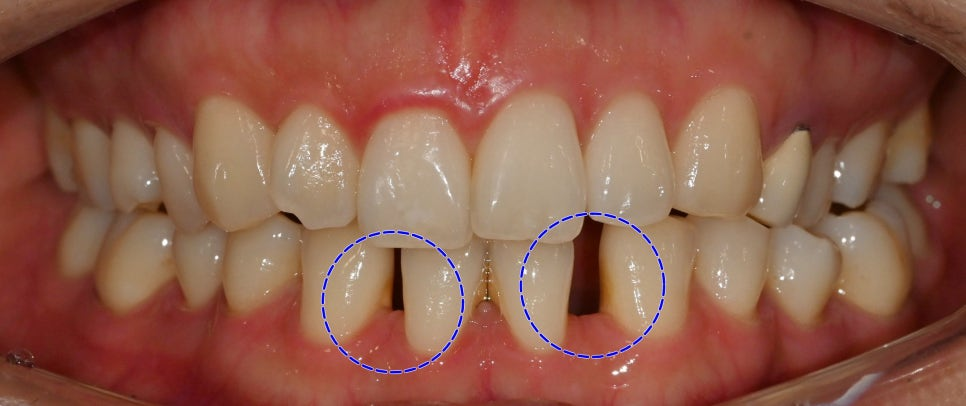

23.10.20

교합면을 보았을 땐

아래 앞니 2개가 결손되어 있으며

사이 공간이 있습니다.

위아래 앞니 사이 거리가 과도합니다.